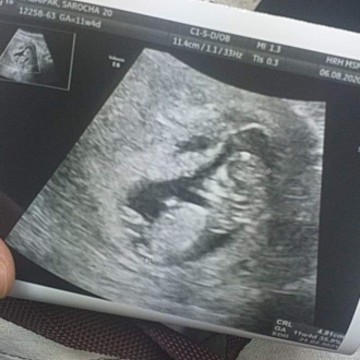

ของเราตอน 11+4 W คะ ตอนนี้ 18+6 แล้ว🥰

ภาพตอน12วีค3วันค่ะ